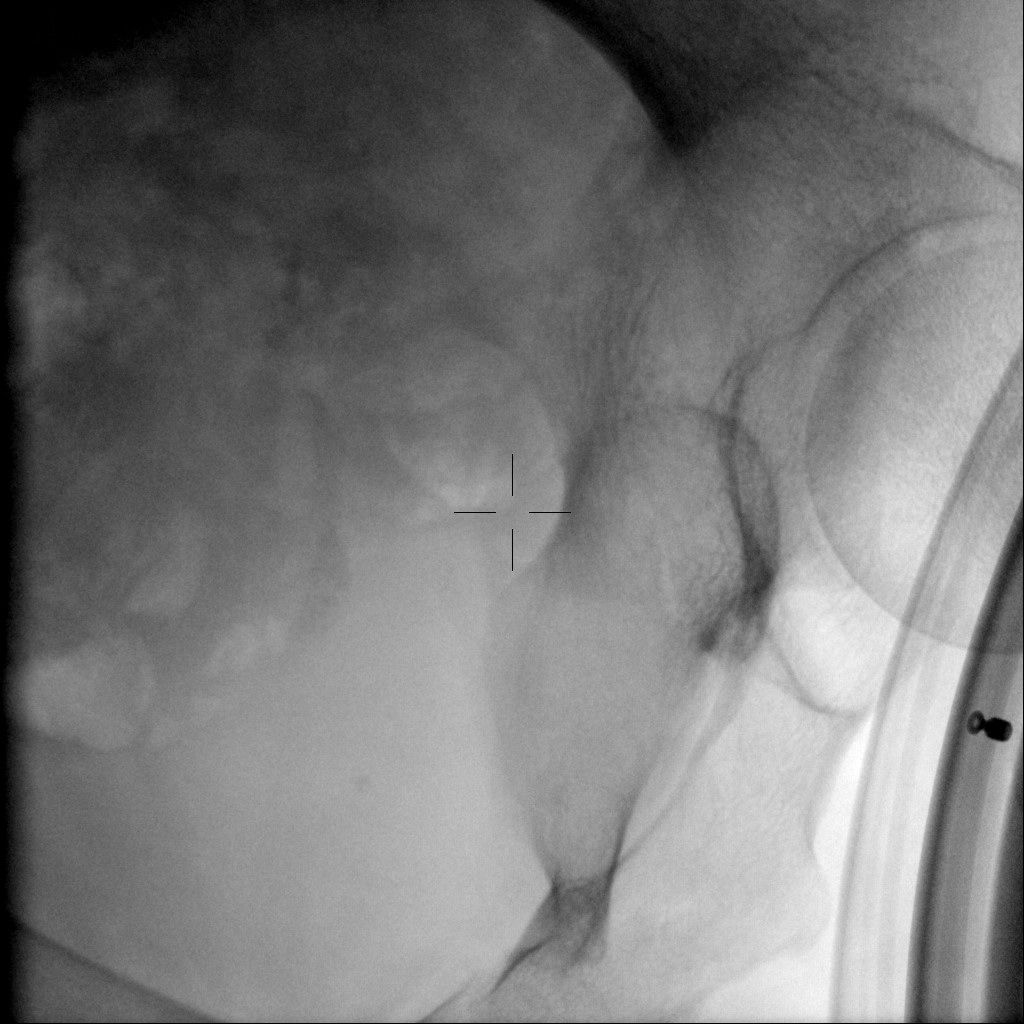

Complete fragmentation of a distal ureteral stone by #ESWL. Radiological and Ultrasound verification. Small stones are also fun!! @FPuigvert @oangerri @koey_kana @paoloverri05 @a_bravo_balado @joanfundi